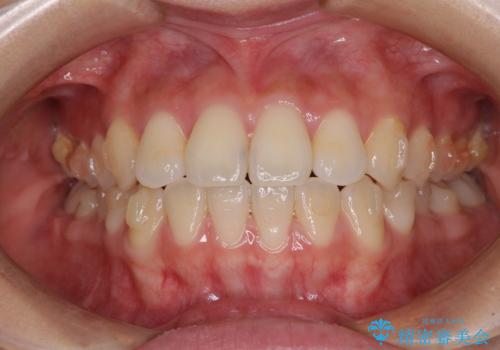

- 前歯のクロスバイトが気になり、インビザラインによる矯正治療を希望して来院された患者様です。

上顎側切歯(上の真ん中から2番目の歯)が舌側転位している場合、インビザラインでは仕上げきれないことが多く、更には無理して動かそうとすると歯髄壊死を起こすリスクが高いと言われています。

インビザラインで歯列を移動する前に、上顎前歯をワイヤー矯正で整え、その後上下歯列をインビザラインにて矯正治療を行うこととしました。

舌側転位している側切歯特有の、切縁の位置が不揃いであったり、根元が内側に引っ込んだ状態であったりという、インビザライン独特の仕上がりになることなく、きれいに整った歯列とすることができました。